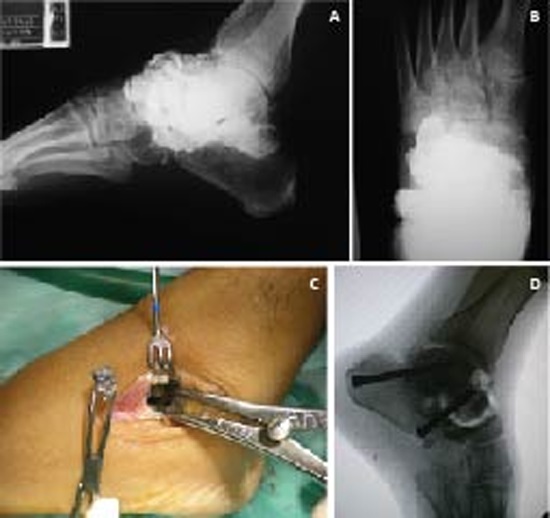

The patient was a 38 year old male with a 3-year history of evolving paroxysmal abdominal pain, postprandial emesis and weight loss. Medical management with partial improvement reported. Progress accompanied by exacerbation of symptoms, bizarre behavior, aggression and seizures. The patient was initially wounded 15 years ago with a shot to the foot. Smoking and drinking to intoxication was reported. Physical examination showed decreased muscle strength with predominantly at C5 -T1 levels. Achilles hyporeflexia. The blood count and peripheral blood smear showed hypochromic microcytic anemia. Lead Levels were: 90.3 µg/dL. Radiograph of foot evidences multiple metal fragments at the midfoot joints. Osteoarthritis of the calcaneocuboid joint, Talo-navicular and subtalar (Fig. 2A). Diagnosis of blood poisoning, starting chelation with EDTA (50 mg/kg/day) for 7 days ago. It is taken to surgery for removal of projectiles lodged and hindfoot arthrodesis (Figs. 2B-D).